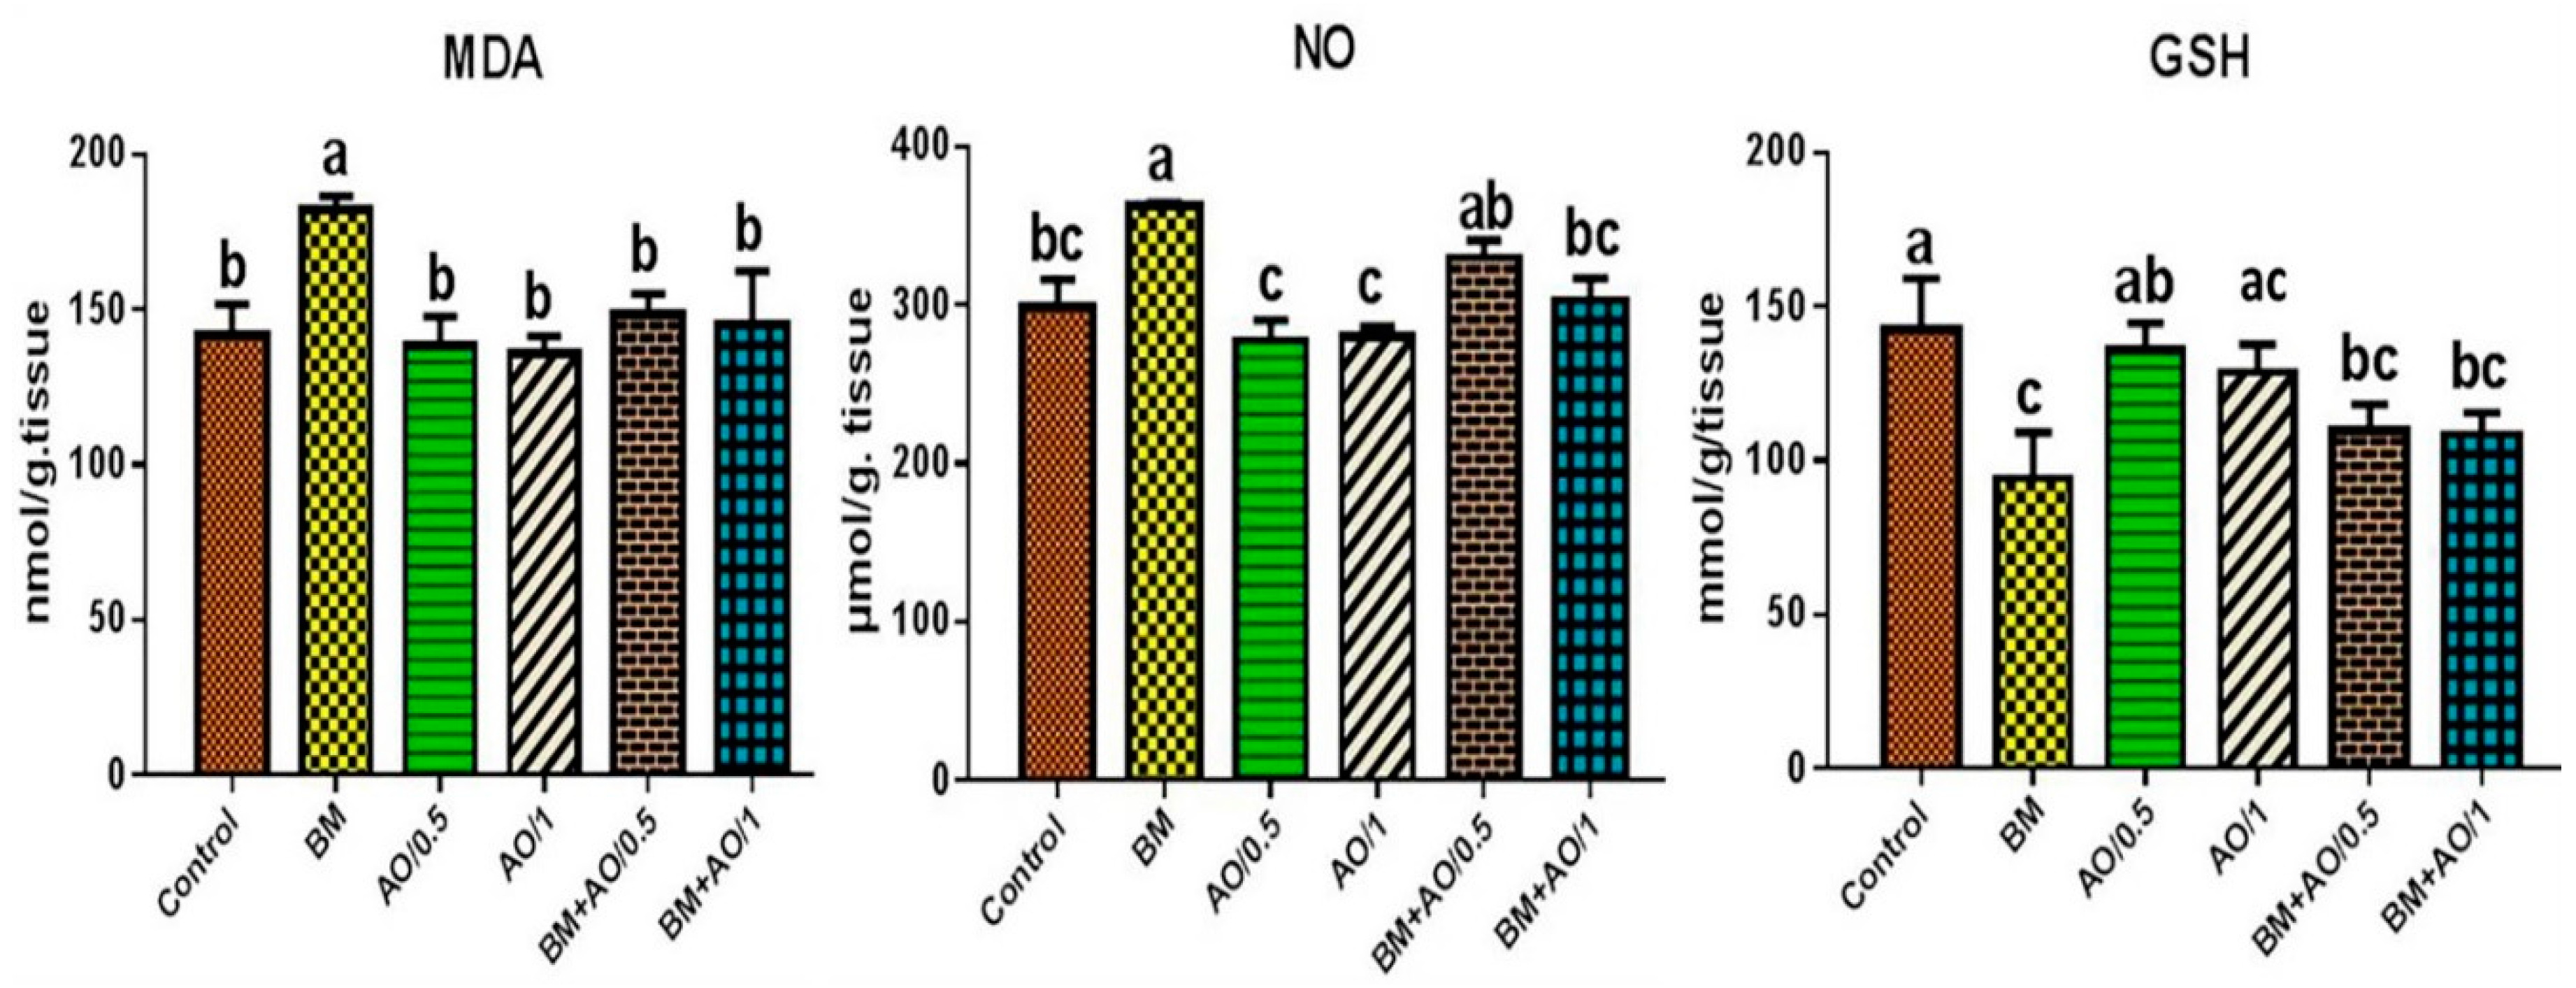

3.5. Argan Oil Improved Betamethasone-Induced Alterations in Renal Oxidant/Antioxidant Biomarkers of Rats